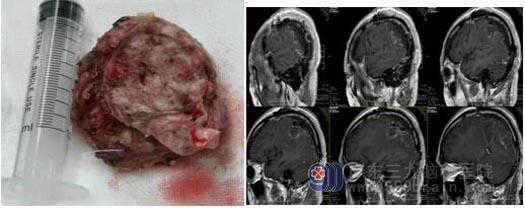

▲术中切除肿瘤标本 ▲术后复查ME见中瘤完全切除

病理结果显示:脑膜皮细胞型脑膜瘤,WHO1级(良性肿瘤)。术后,叶先生恢复良好,很快就可以下地走路了。一周后,未出现任何并发症出现叶大叔高兴地说:可以安心地回家过年了!